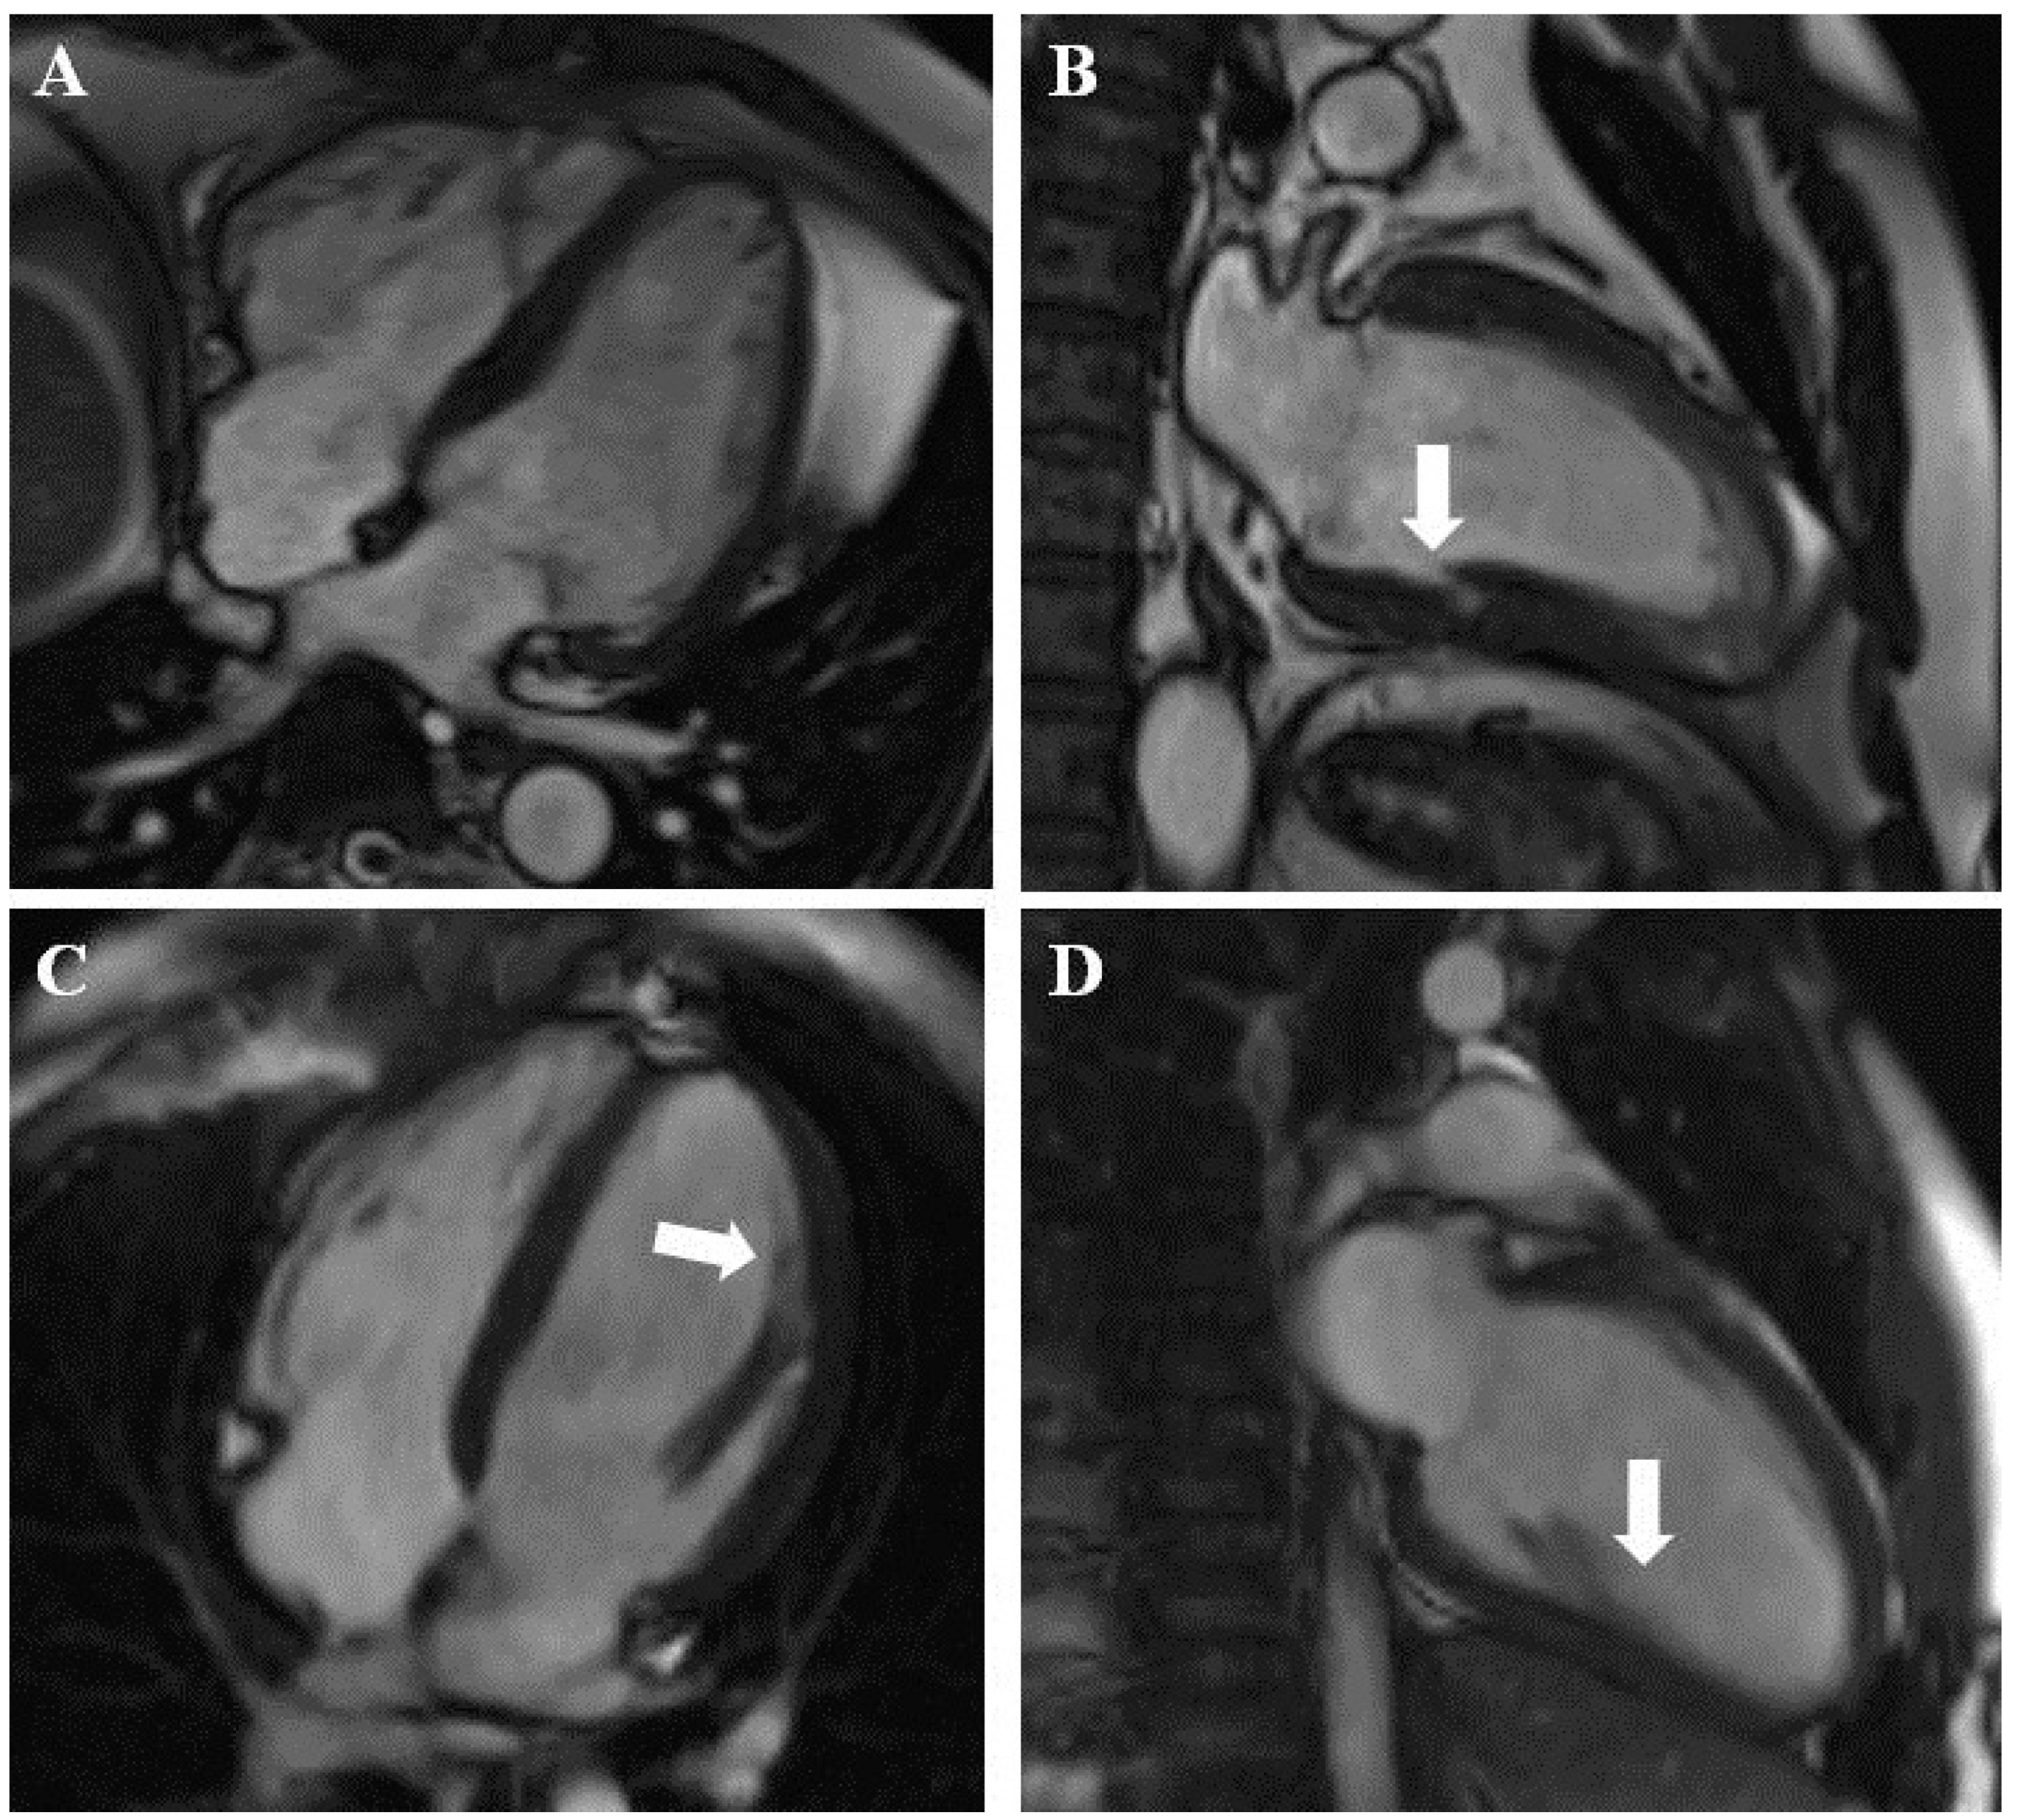

Figure 2.

(A,B) Other, nonspecific cardiomyopathy: abnormal left ventricular muscle structure and myocardial crypt (arrow) in the posterior wall. (C,D) Example of normal CMR study. The broad base of the anterolateral papillary muscle (arrows) may mimic hypertrabeculation.

In 108 patients (suspected group, 98 (37.8%); confirmed group, 10 (13.5%)) the CMR scan was normal or nonspecific (Figure 2C,D).

CMR provided better insight into the myocardial structure than echocardiography and led to the differentiation of myocardial hypertrabeculation and other structures (Figure 2). CMR also had the ability to characterize the myocardial structure and the presence, type, and extent of fibrosis. LGE imaging was crucial in the diagnosis of coronary heart disease and amyloidosis and was helpful in the diagnosis of other diseases, such as HCM (Figure 1).